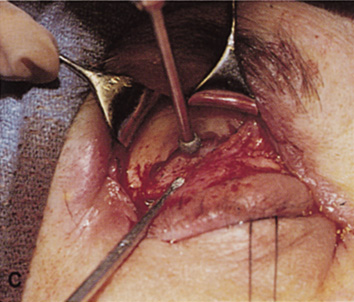

orbital rim can be elevated and osteotomies and removal of the lateral

wall still can be carried out. | Fig. 9. A,B. Coronal and axial CT images of a large intraconal neoplasm. C. Because it was felt to represent a well-encapsulated cavernous hemangioma, this

lesion was a candidate for removal via an eyelid crease orbitotomy

without bone removal. The eyelid crease incision marked. D. Incision made with scalpel. E. Orbicularis muscle is tented up and incised to expose the underlying septum. F. Dissection of a skin-muscle flap deep to orbicularis exposes the orbital

septum and superior orbital bony rim. G. Cutting cautery is used to incise periosteum along the superior and lateral

rims; finger palpation of the bone helps to direct this incision. H. Periorbita is elevated along the mesial surface of the lateral orbital

rim in order to expose the deep orbital tissues. I. The cavernous hemangioma is visualized in the wound. Retraction is provided

by one or more malleable retractors. J. Cryoprobe is affixed to the hemangioma to facilitate manipulation of the

lesion. K. Large cavernous hemangioma after removal through the eyelid crease incision

which was accomplished without bone removal. L. Periorbita is reattached over the lateral rim. M. The eyelid crease incision is closed with a running suture. |